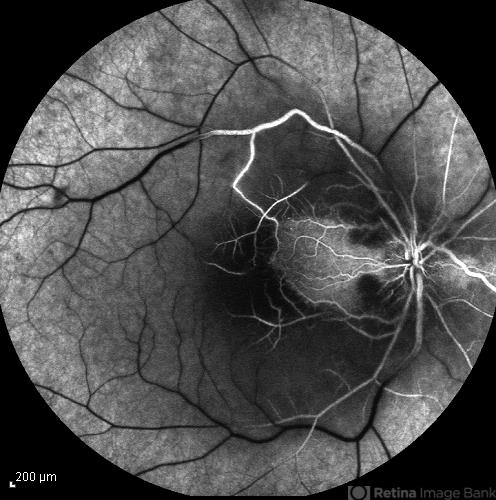

- central retinal artery occlusion (CRAO), cilioretinal sparing

- Mid arteriovenous phase FA image of the right eye of a 34-year-old man with sudden drop of vision due to CRAO. The macula is involved despite cilioretinal artery sparing .